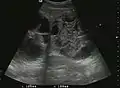

US examination is required to detect liver metastases in patients with oncologic history. In addition, the method can incidentally detect metastases in asymptomatic patients. Early identification (small sizes, small number) is important to establish an optimal course of treatment which can be complex (chemotherapy, radiofrequency ablation, surgical resection) but welcomed. In addition, discrimination of synchronous lesions that have a different nature is also important knowing that up to 25–50% of liver lesions less than 2 cm detected in cancer patients may be benign . US sensitivity for metastases detection varies depending on the examiner's experience and the equipment used and ranges between 40 and 80% . Sensitivity is conditioned by the size and acoustic impedance of the nodules. For a lesion diameter below 10 mm US accuracy is greatly reduced, reaching approx. 20%. Other elements contributing to lower US performance are: excessive obesity, fatty liver disease, hypomobility of the diaphragm, and certain patterns of hyperechoic or isoechoic metastases that can be overlooked or can mimic benign conditions. Conventional US appearance of metastases is uncharacteristic, consisting of circumscribed lesions, with clear, imprecise or "halo" delineation, with homogeneous or heterogeneous echo pattern. They can be single (often liver metastases from colonic neoplasm) or multiple. Echogenity is variable. When increased, they can compress the bile ducts (which may be dilated) and the liver vessels. Liver involvement can be segmental, lobar or generalized. In this situation a pronounced hepatomegaly occurs. Generally, metastases have non-characteristic Doppler vascular pattern, with few exceptions (carcinoid metastases). Cyst-adenocarcinoma metastases due to semifluid content may have a transonic appearance. When increasing, they can result in central necrosis. CEUS examination is a real breakthrough for detection and characterization of liver metastases.

Increased performance is based on identifying specific vascular patterns during the arterial phase and seeing metastases in contrast to normal liver parenchyma during the sinusoidal phase. CEUS increased accuracy is due to the different behavior of normal liver parenchyma (captures CA in Kuppfer cells) against tumor parenchyma (does not contain Kuppfer cells, therefore CEUS appearance is hypoechoic). To this adds the particularities of intratumoral circulation represented by a reduced arterial bed compared to that of the surrounding normal liver and the absence of the portal vessels . In terms of vascularity, metastases can be hypovascular (in gastric, colonic, pancreatic or ovarian adenocarcinomas) with hypoechoic pattern during arterial phase, and similar during portal venous and late phases, respectively hypervascular (neuroendocrine tumors, malignant melanoma, sarcomas, renal, breast or thyroid tumors) with hyperechoic appearance during arterial phase, with washout during the portal venous phase and hypoechoic pattern 30 seconds after injection.